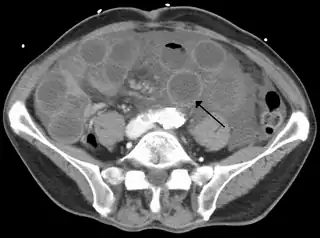

![]() TC de una isquemia de intestino delgado debida a trombosis de la vena mesentérica superior. Se muestra el intestino dilatado y la pared engrosada. | ||